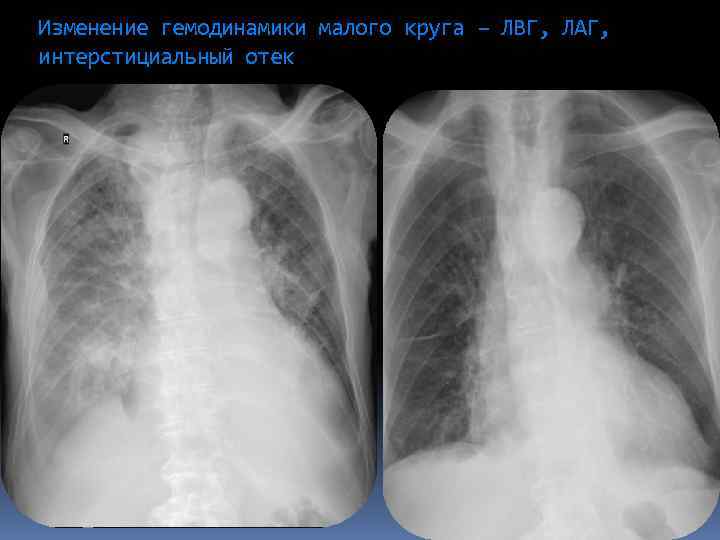

Изменение гемодинамики малого круга – ЛВГ, ЛАГ, интерстициальный отек

Изменение гемодинамики малого круга – ЛВГ